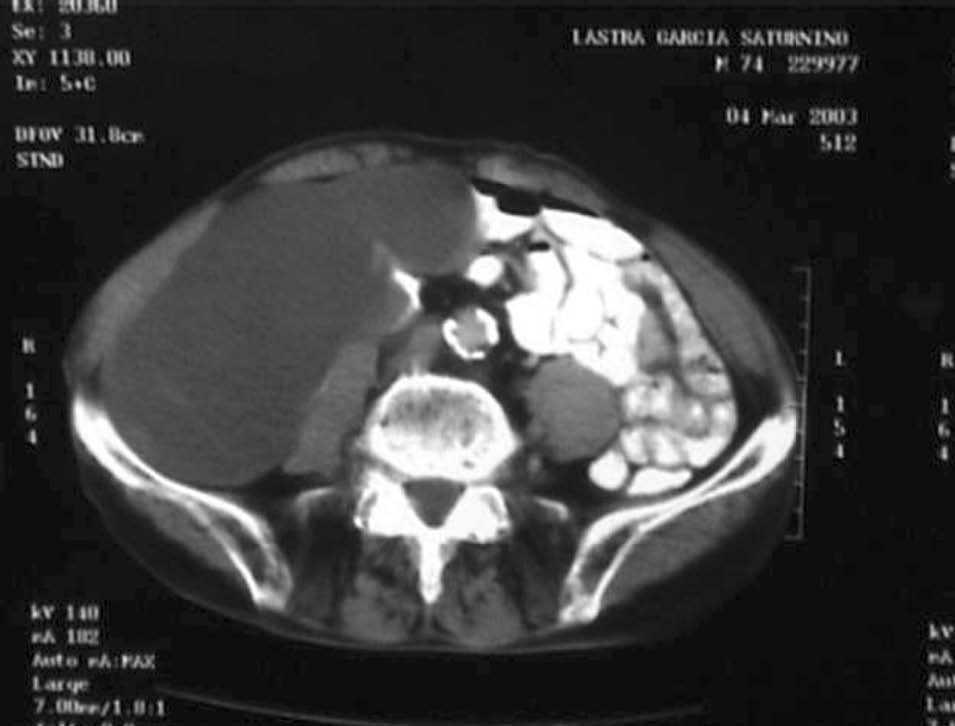

Varón de 76 años que presenta una masa blanda, no pulsátil e indolora en el hemiabdomen derecho. La tomografía computarizada (TC) helicoidal muestra una tumoración quística infracecal de 20 cm (fig. 1). En la punción-aspiración con aguja fina (PAAF) se obtiene material mucoide sin signos citológicos de malignidad. Se practicó una hemicolectomía derecha por una gran tumoración quística dependiente del ciego (fig. 2) cuyo informe anatomopatológico correspondió a un cistoadenoma apendicular.

El mucocele apendicular es la dilatación quística del apéndice debido a la acumulación progresiva de material mucinoso como consecuencia de una obstrucción proximal de su luz. Se clasifican en 4 tipos histológicos: quistes de retención, hiperplasia mucosa, cistoadenomas y cistoadenocarcinomas. En los cistoadenomas la mucosa está revestida por un epitelio columnar con proyecciones papilares productores de mucina. Pueden originarse de novo o estar precedidos por un mucocele simple, no infiltran las paredes del apéndice y no producen metástasis, lo que se consideran rasgos de benignidad. Sin embargo, los cistoadenomas pueden presentar una transformación maligna en algunas circunstancias o tras una apendicectomía. La PAAF, aunque útil en la orientación diagnóstica, supone un riesgo de diseminación en caso de rotura. La apendicectomía es el tratamiento adecuado en los mucoceles simples; no obstante, este caso, debido al gran tamaño y al abundante material mucinoso similar al observado en los seudomixomas peritoneales, nos indujo a realizar un procedimiento más radical.